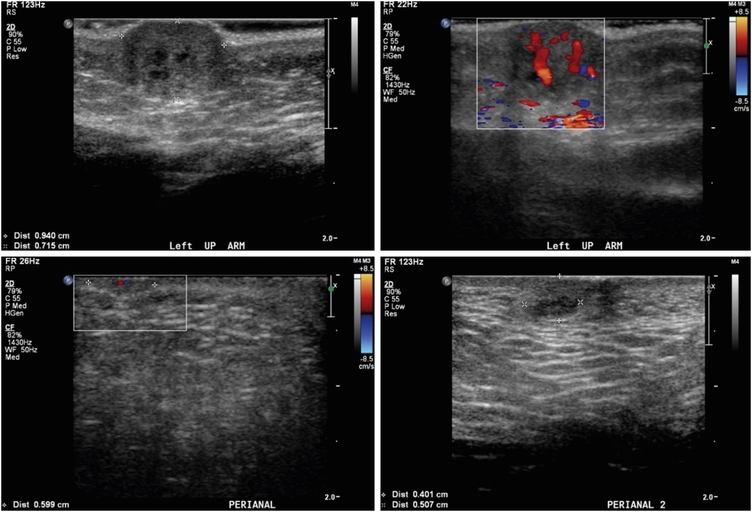

Laboratory evaluations, including a complete blood count with platelet, hemoglobin, coagulation battery, and D-dimer assessment, and liver function, renal function, serum electrolytes, and thyroid function tests, were within normal limits or negative. Abdominal ultrasonography showed mild left pelviectasis (7 mm). Soft tissue mass ultrasonography showed multiple hypoechoic solid masses with markedly increased vascularity, suggesting hemangiomas (Fig. 2). Whole body magnetic resonance imaging (MRI) showed a numerous enhancing skin, subcutaneous, and muscular lesions throughout the body, and a multiple lobulated enhancing mass with a central non-enhancing portion along the anus and buttock areas and involving the right sided of the anal sphincter. Brain MRI demonstrated multiple variably-sized enhancing lesions in the right cerebellum, right medial temporal lobe, left thalamus, and right parietal lobe, with marked perilesional edema; the largest in the right parietal lobe measured up to 6.5 mm (Fig. 3). Echocardiography showed unremarkable findings. Neurologic and eye examinations revealed no abnormalities. To confirm whether multiple hemangiomas are related to genetic abnormality, we additionally performed chromosomal analysis. The test showed no chromosomal structural abnormalities and was 46, XY, which is normal karyotype.

Fig. 2

Soft tissue mass ultrasonography before treatment.